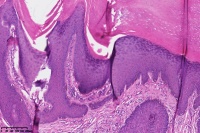

额部包块,脂溢性角化症色素型?

男

88岁

额部包块

考虑老年性角化病。

脂溢性角化病。